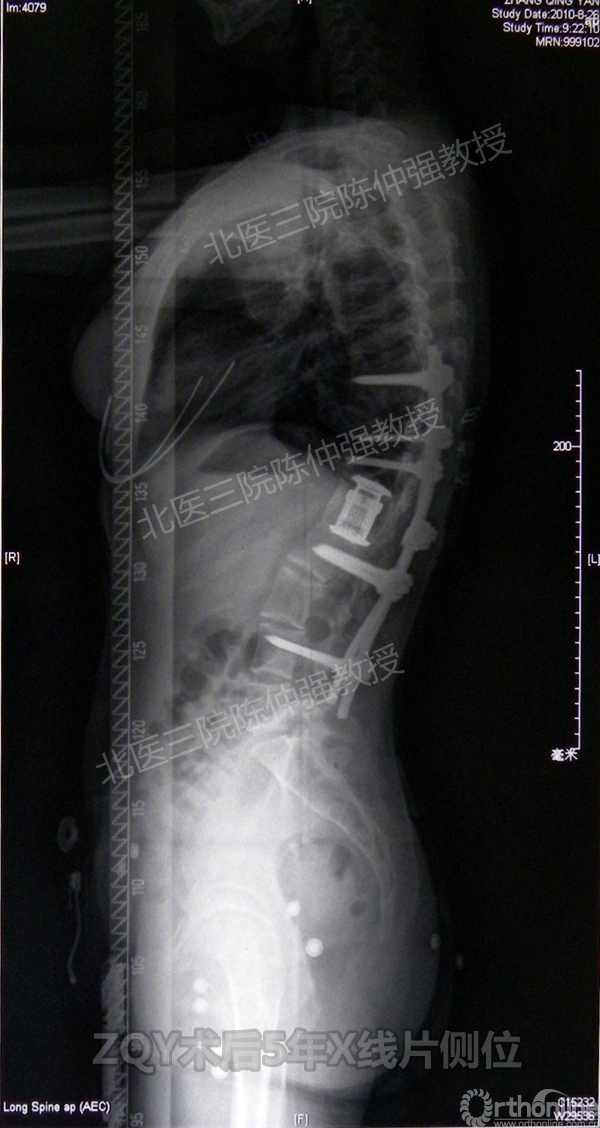

ZQY术后5

患者女性17岁,胸腰椎陈旧结核性侧后凸畸形,局部呈“麻花状”扭转,无神经功能受损表现。2005年,陈仲强教授带领团队实施后路+侧前方联合入路脊柱节段切除、双轴旋转矫形术。术后患者外观显著改善,神经功能正常。术后随访证实患者截骨矫形节段骨性融合良好,矫形效果持续良好。